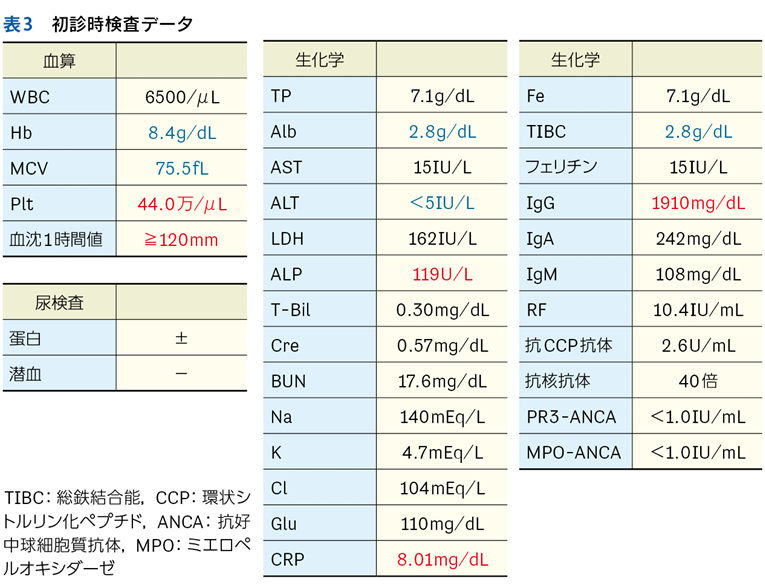

▶ 表3にフレーミングの例をいくつか示す。